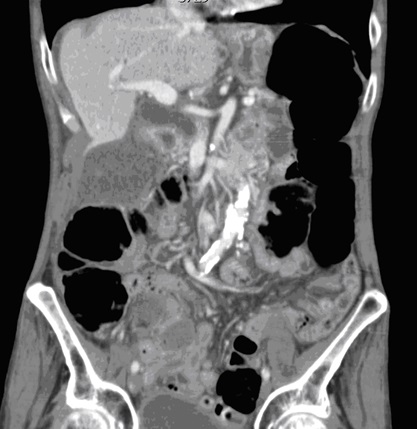

Image TDM :

Image radiologiquer TDM de syndrome de Mirizzi est la

presence de calcul et une epaisissement de la paroi vesicule

biliaire rehaussement hyperdense par le contrast . La dilatation de voie

biliaire pricipale ( canal hepatique commune ) peut se

en voyait . .

Meme cas en coupe coronal ( frontal ) :

Image de calcul hyperdense se en voyait tres net (

fleche rouge ) avec image de vesicule biliaire

inflamee et la dilatation de canal hepatique commun |